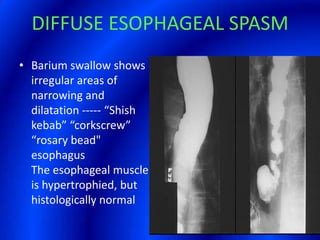

This document provides information about a barium swallow procedure. It begins with an introduction and overview of the embryology and anatomy of the pharynx and esophagus. It then describes the procedure itself, including preparation, technique, views obtained, and indications. Specific conditions that may be examined include pharyngeal and esophageal webs, foreign body impaction, scleroderma, dysphagia, mediastinal masses, and carcinoma. Diagrams are provided to illustrate normal anatomy and various pathological findings.